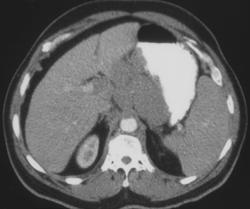

Gastric Leiomyosarcoma